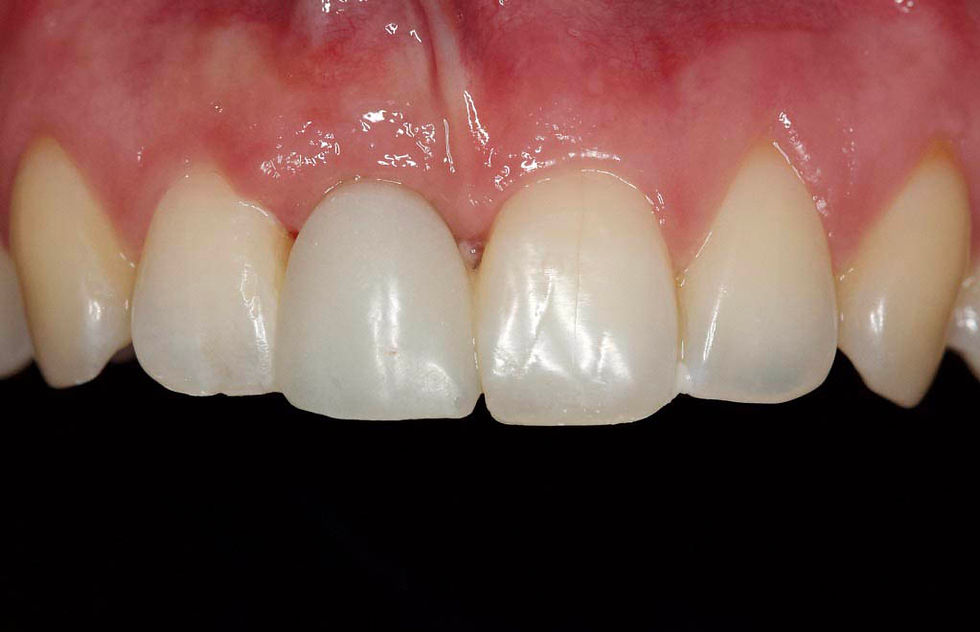

After 5 months from the extraction, the guided surgery implant positioning is planned. Frontal clinical image shows that the distal papilla of the site 1.1 is more apical than the mesial and the contralateral papillae.